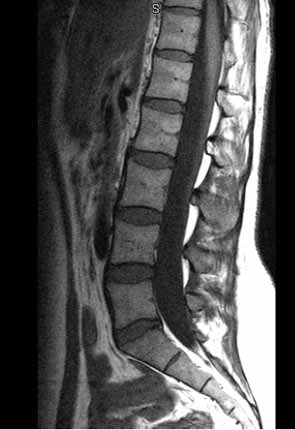

RMN normal de la columna lumbar

Nota: Las imágenes se muestra para fines ilustrativos. No trate de sacar conclusiones comparando esta imagen con otras en el sitio. Solamente los radiólogos calificados deben interpretar las imágenes.